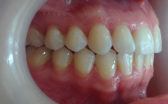

- After

At the end of four months, my front teeth were straight and I was able to have my braces removed! I am extremely happy with my Cfast end result and it was all worth it.